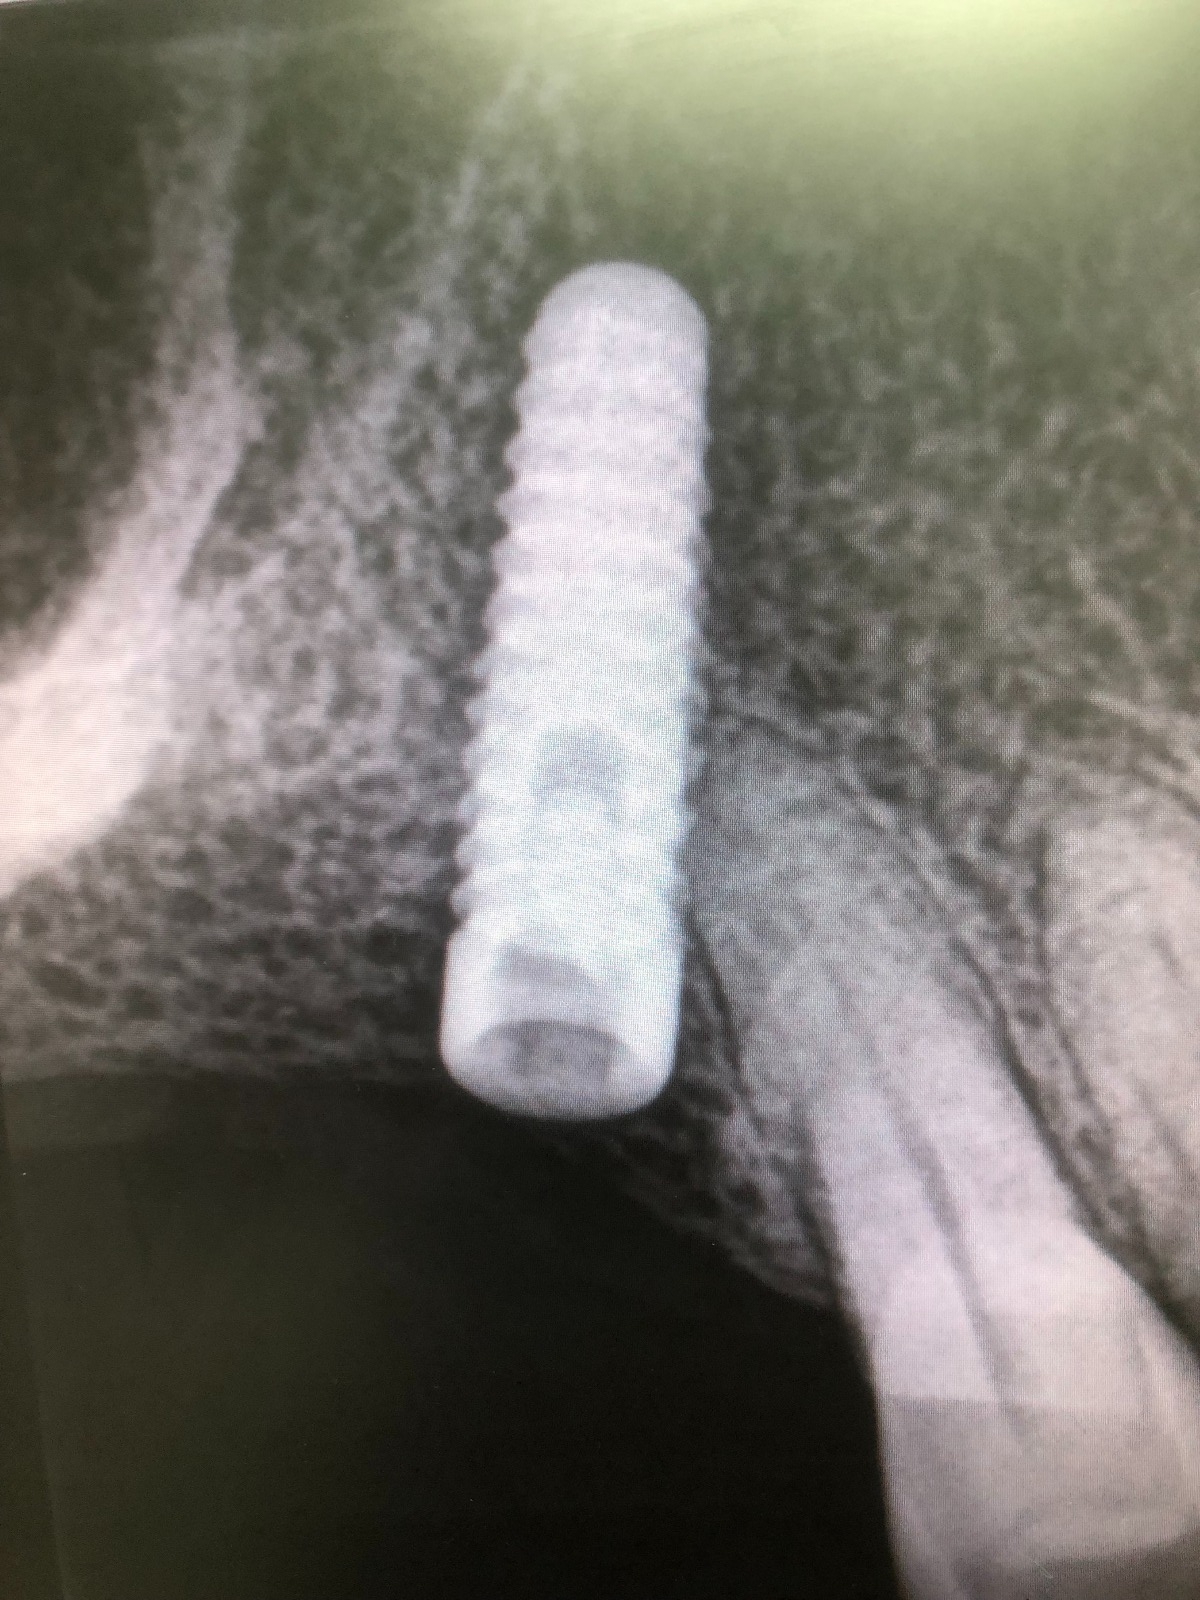

Como hemos comentado es un molar, es decir, una pieza dental en la zona posterior de la boca y con una posición del implante muy inclinada para poder esquivar el seno maxilar, lo cual dificulta mucho el trabajo.

Exponemos nuevo caso de paciente con una fractura del tornillo pasante sobre un implante unitario molar. El tornillo pasante es la parte fundamental de la conexión y es el que está roto dentro y gripado, de tal forma que no pudimos extraer con el aparato de ultrasonido.